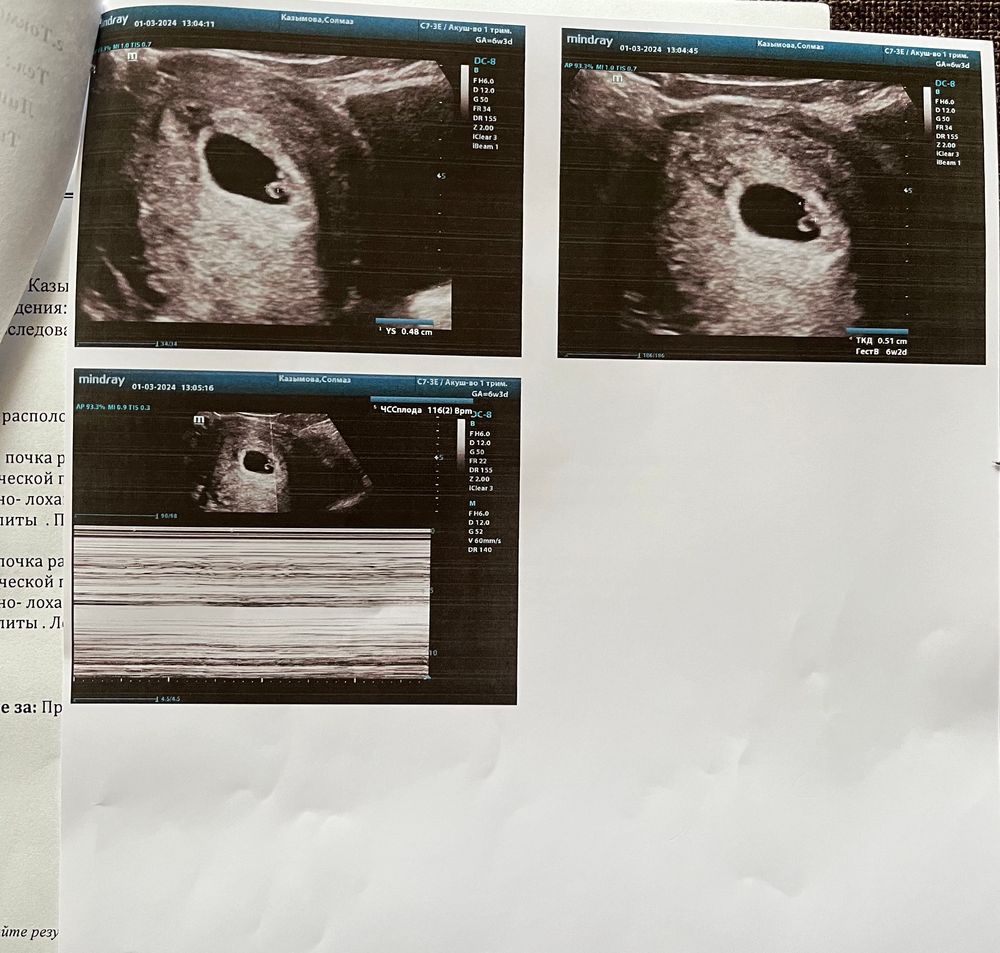

УЗИ 6 неделек + 2

Вот и послушали сердечко нашего малыша ❤️

Мария , спасибо ❤️ у меня почему-то сравнялся эмбриональный и акушерский.

когда пошла на первое узи, разница была неделю (4 эмбриональных, 5 акушерских).

а в этот раз сравнялось - 6 акушерских и эмбриональных